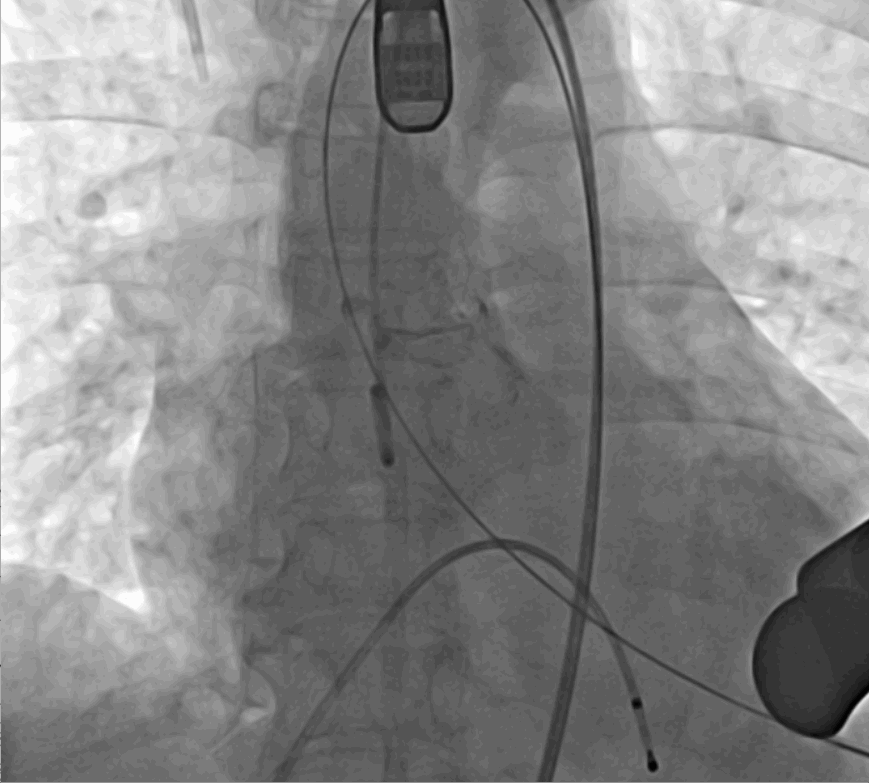

術前DSA影像圖

術中釋放定位鍵后DSA影像圖